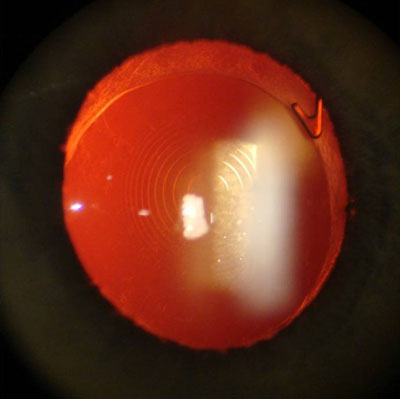

Meibomitis associated with evaporative dry eye

Source: John D. Sheppard, MD

A retrospective analysis suggests oral azithromycin may be beneficial.